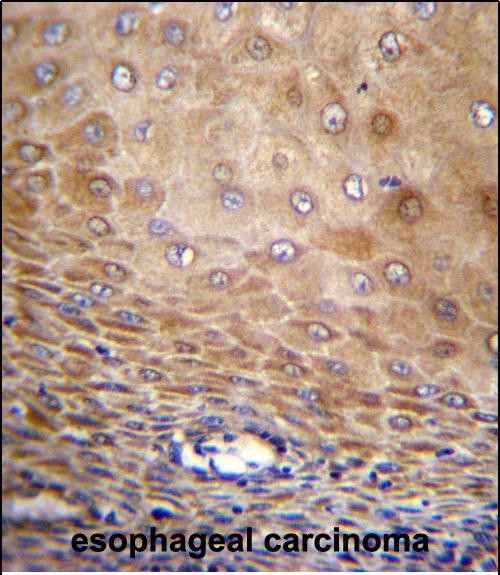

IHC 1/100-1/500 Human,Mouse,Rat

TMEM43 antibodies, typically raised in rabbits or mice, are used in techniques like Western blotting, immunohistochemistry (IHC), and immunofluorescence (IF) to study TMEM43 expression, localization, and dysfunction in disease models. Commercial antibodies are validated for specificity to human, mouse, or rat TMEM43 isoforms. Research utilizing these antibodies has advanced understanding of TMEM43's interaction with nuclear lamina proteins (e.g., emerin) and its role in ARVC5. aiding therapeutic discovery. However, challenges remain in standardizing antibody validation and elucidating TMEM43's full mechanistic spectrum across tissues.